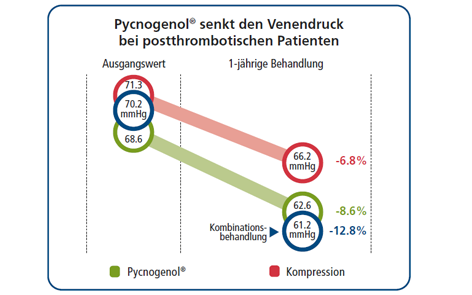

In einigen Fällen können allgemeine Schwellungen der Beine sich zu einer gefährlichen chronisch-venösen Insuffizienz (CVI) entwickeln, die, wenn sie nicht behandelt wird, zu Komplikationen und Ulzerationen (Geschwürbildungen) führen kann. Bisher wurden 15 klinische Studien mit insgesamt 784 Patienten zu venöser Insuffizienz und Pycnogenol® veröffentlicht. Die hohe Wirksamkeit von Pycnogenol® als Therapie der venösen Insuffizienz war in der Tat in zahlreichen Studien so deutlich, dass es regelmäßig zusammen mit bekannten Arzneimitteln für gesunde Venen untersucht wird. Dies wird in einer deutschen Doppelblind-Vergleichsstudie mit 40 CVI-Patienten deutlich. Es wurde gezeigt, dass Pycnogenol® in einer geringeren Dosierung Ödeme der unteren Extremitäten wirksamer verringerte und die Symptome der CVI wirksamer linderte als Rosskastaniensamenextrakt. Darüber hinaus untersuchte eine klinische Studie mit 70 Patienten die Wirkung von Pycnogenol® bei der Behandlung der venösen Insuffizienz im Vergleich zu Troxerutin, einem wasserlöslichen Derivat von Rutin, einer üblichen Behandlung für die CVI. Nach einer Behandlung über 60 Tage erzielte eine Kombination aus Troxerutin und Pycnogenol® signifikantere Ergebnisse bei der Linderung der Symptome der CVI als Troxerutin alleine.

Zu den weiteren bemerkenswerten Forschungsarbeiten gehört eine Studie mit 211 Passagieren auf einem Langstreckenflug (7-12 Stunden), die Pycnogenols Wirksamkeit bei der Vorbeugung von Thrombosen zeigte. Die Passagiere nahmen zwei 100mg-Kapseln Pycnogenol® zwei bis drei Stunden vor dem Abflug und weitere zwei Kapseln nach sechs Stunden während des Flugs ein. Eine weitere Kapsel wurde am nächsten Tag nach der Ankunft eingenommen. Während in der Placebo Kontrollgruppe fünf Fälle von (transienten) Thrombosen auftraten, entwickelte keiner der Passagiere, die Pycnogenol® einnahmen, während des Flugs eine Thrombose.